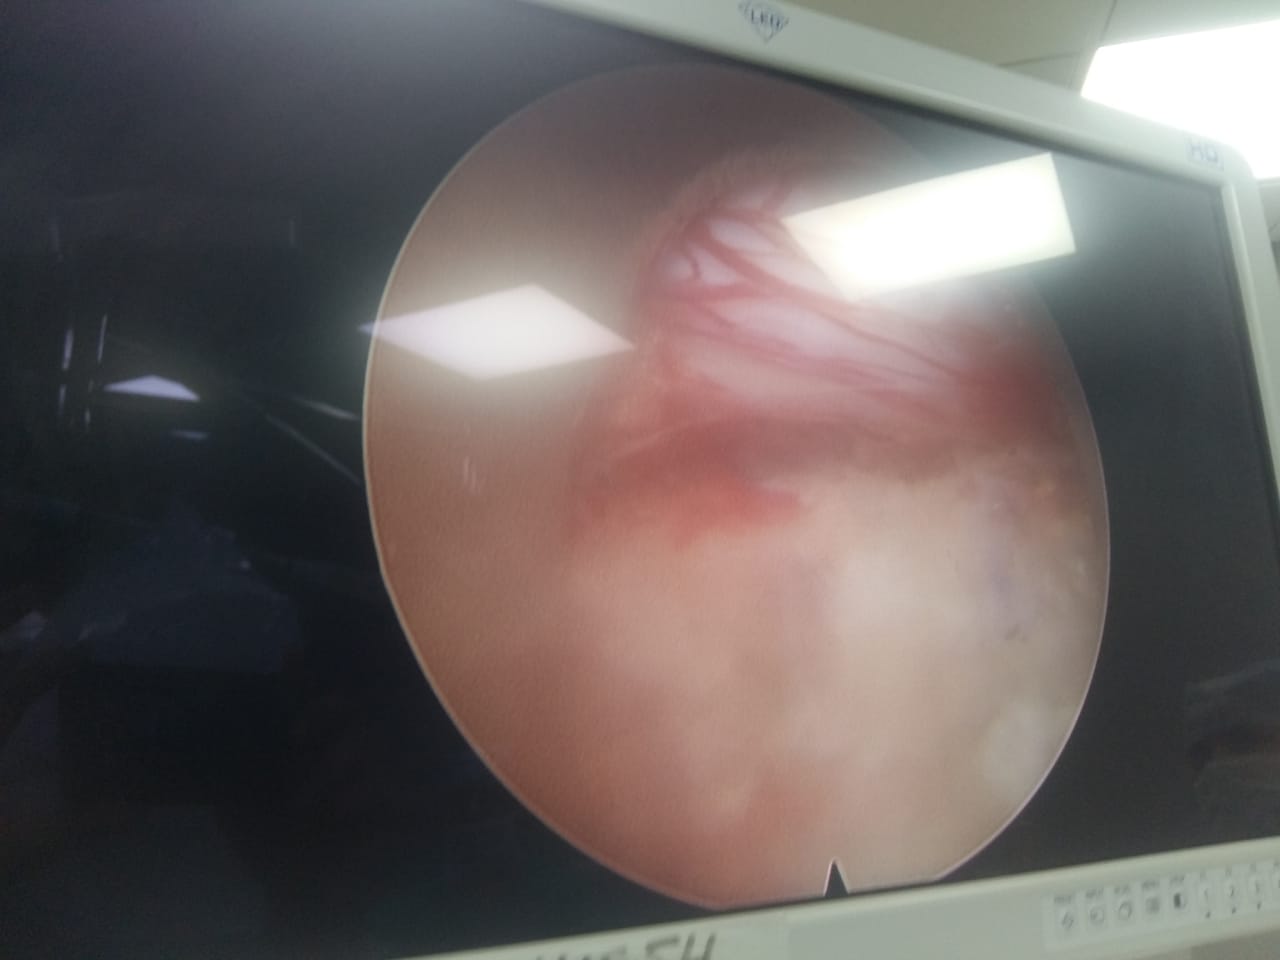

Endoscopic view of spinal canal

Endoscopic surgery in progress